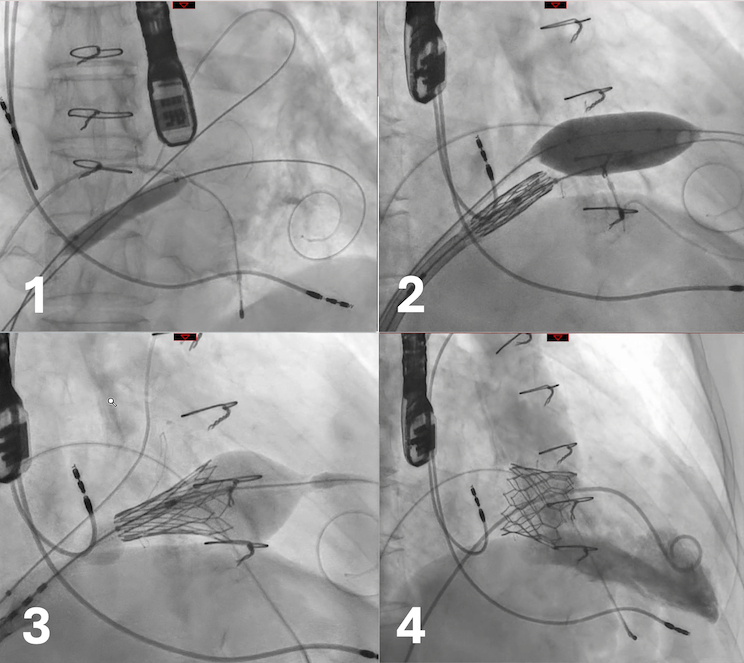

The heart team opted for mitral ViV with a Sapien Ultra 29mm valve. Using a Swartz 8F sheath and BRK needle, a posteroinferior transseptal puncture was performed, and a 0.035" guidewire was advanced to the LV and exchanged for a pigtail catheter. A Safari extra-support guide was then positioned in the LV, and a second stiff wire was placed in the superior left pulmonary vein. Due to difficulty advancing the prosthesis, sequential septal dilations were performed with 8.0 mm and 10.0 mm balloons. The Sapien Ultra was then advanced across the septum but could not cross the stenotic surgical valve. The wire was repositioned from the pulmonary vein to the LV, and valvuloplasty was done with a 20×30 mm AltoSa balloon. The valve was then successfully navigated and implanted under rapid pacing with nominal deployment.

Post-procedure 3D echo confirmed good valve dynamics with a mean gradient of 2 mmHg and visualization of a ruptured surgical leaflet. At 4-month follow-up, the patient remains in NYHA class I, with no adverse events.